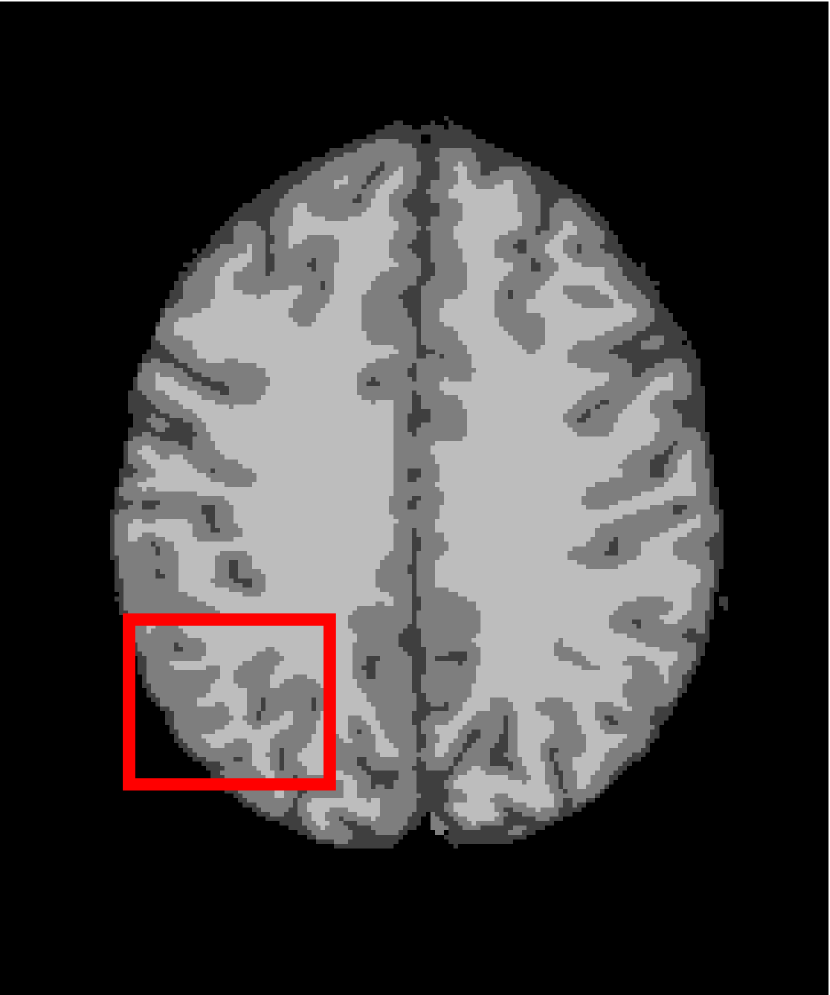

4.4.2 Results on Medical Images

Next, we representatively segment five medical images from BrianWeb. They are represented as five slices in the axial plane with a sequence of 70, 80, 90, 100 and 110, which are generated by T1 modality with slice thickness of 1mm resolution, 9% noise and 20% intensity non-uniformity. Here, we set c=4𝑐4c=4 for all cases. The comparison between WRFCM and its peers are shown in Fig. 9 and Table II. The best values are in bold.

Figure 9: Segmentation results on five medical images. The parameter: ϕ=5.35italic-ϕ5.35\phi=5.35. From top to bottom: noisy images, ground truth, and results of FCM_S1, FCM_S2, FLICM, KWFLICM, FRFCM, WFCM, DSFCM_N, and WRFCM.

TABLE II: Segmentation performance (%) on medical images in BrianWeb

Algorithm Fig. 9 column 1 Fig. 9 column 2 Fig. 9 column 3 Fig. 9 column 4 Fig. 9 column 5

SA SDS MCC SA SDS MCC SA SDS MCC SA SDS MCC SA SDS MCC

FCM_S1 75.756 97.852 96.225 75.026 98.109 96.656 79.792 98.452 97.334 81.887 98.614 97.680 81.869 94.254 90.947

FCM_S2 75.769 98.119 96.664 74.970 98.176 96.765 79.886 98.458 97.338 82.073 98.625 97.695 81.788 98.223 97.195

FLICM 74.998 98.070 96.568 74.185 98.122 96.660 79.099 98.515 97.432 81.447 98.627 97.691 81.668 98.273 97.260

KWFLICM 74.840 98.259 96.878 73.839 97.860 96.190 79.560 98.453 97.316 81.887 98.482 97.443 81.370 98.297 97.286

FRFCM 75.853 97.620 95.775 75.514 97.660 95.830 80.283 98.278 97.013 81.852 98.319 97.171 81.666 98.079 96.945

WFCM 75.507 97.124 94.957 74.471 97.213 95.045 79.316 97.845 96.283 81.358 97.546 95.211 81.452 95.247 92.501

DSFCM_N 76.400 92.325 86.262 75.288 91.574 85.095 79.861 97.678 95.996 81.831 93.304 88.829 81.750 94.302 91.024

WRFCM 82.317 98.966 98.147 82.141 98.298 96.970 83.914 98.963 98.202 83.533 99.170 98.603 84.615 98.429 97.511

By a view of the marked red square in Fig. 9, we find that FCM_S1, FCM_S2, FLICM, KWFLICM and DSFCM_N are vulnerable to noise and intensity non-uniformity. They give rise to the change of topological shapes to some extent. Unlike them, FRFCM and WFCM achieve sufficient noise removal. However, they produce overly smooth contours. Compared with its seven peers, WRFCM can not only suppress noise adequately but also acquire accurate contours. Moreover, it yields the visual result closer to ground truth than its peers. As Table II shows, WRFCM obtains optimal SA, SDS and MCC results for all five medical images. As a conclusion, it outperforms its peers visually and quantitatively.